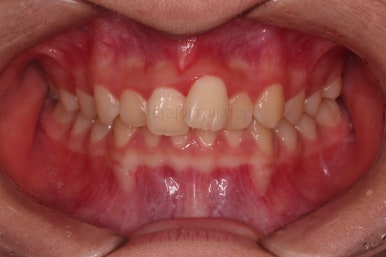

종료 때의 사진입니다.

가지런하고, 교합도 좋으며 과개교합이나 앵글씨 2급 부정교합 부분도 완벽히 좋아졌습니다.

자연스럽게 중앙선도 매우 좋아졌고요.

이제 전후 비교를 해보겠습니다.

웃는 모습도 매우 좋아졌고요.